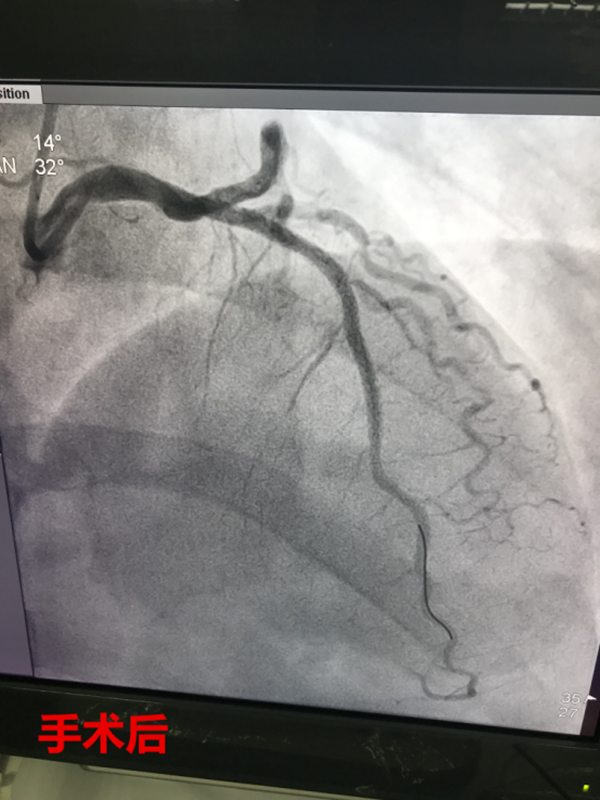

11時12分,路艷主治醫(yī)師護送患者繞行急診科及CCU,直達介入室。徐曉輝主任、耿蓬勃、師軍峰副主任醫(yī)師以及介入室護士郭紀文、于永利、霍貝貝等人員立即就位,手術(shù)開始,穿刺、造影、導(dǎo)絲通過、球囊擴張、支架植入,為患者實施的急診手術(shù)一切都緊張有序的進行……11時45分,手術(shù)順利完成,DtoB時間(患者進入醫(yī)院大門至PCI介入手術(shù)球囊擴張的時間)僅僅26分鐘,遠遠超出了國家對胸痛患者DtoB的時間要求(國家胸痛中心DtoB時間要求<90分鐘)。